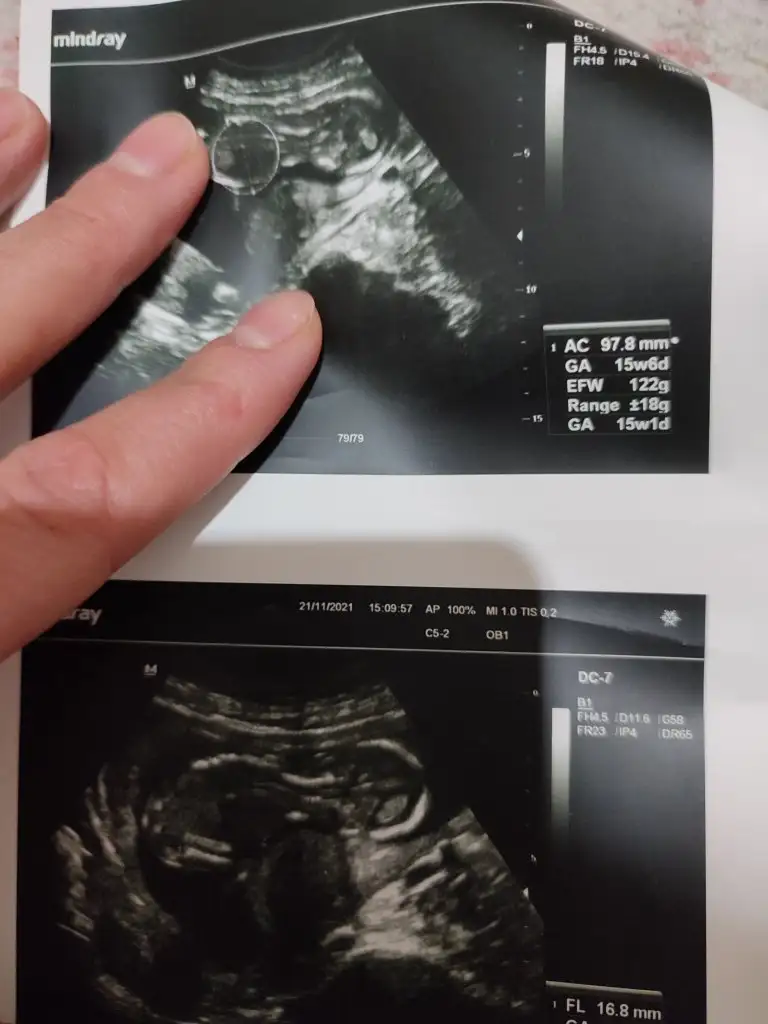

Doktor erkek gibi duruyor dedi ama bakalim net değilEmin olamadım kız gibi sanki

Emin olamadım ama sanki kız gibi

Tahmininiz doğru çıktı haber vermek istedimErkek gibi sanki

Kız gibi sankiIkra meyra

Erkek sankiİkra hanım merhaba 12 hafta görüntülerini ekledim sizce nedir cinsiyeti